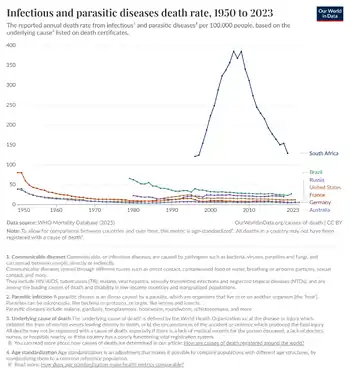

- ↑ "Infectious and parasitic diseases death rate". Our World in Data. Archived from the original on 16 May 2025. Retrieved 22 August 2025.